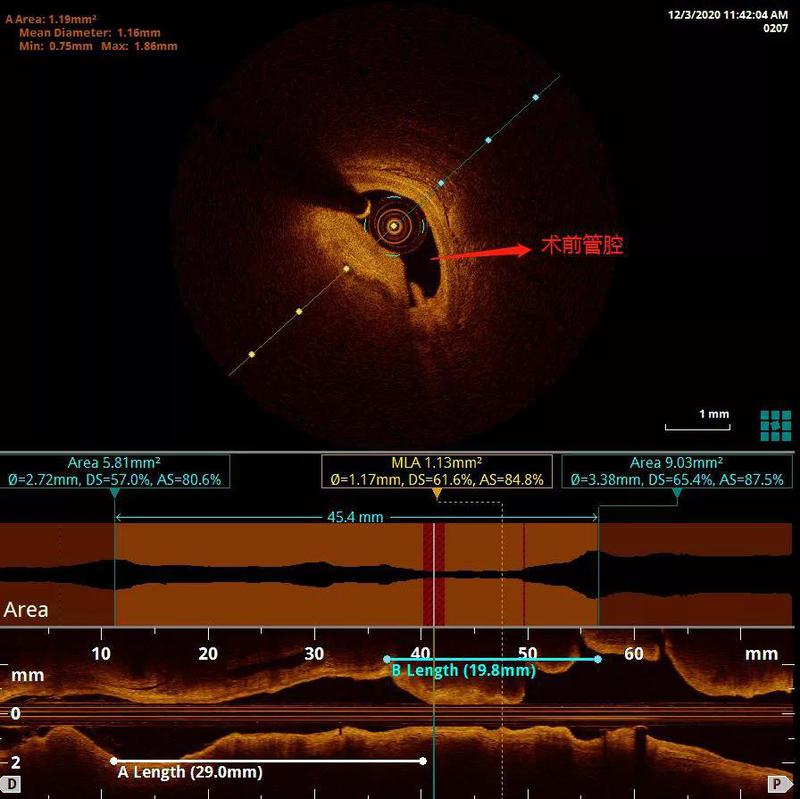

经过OCT检查,评估最小管腔面积约1.13mm2,斑块性质以纤维脂质成分为主,同时,狭窄部位内膜不连续、并可见少量附壁血栓,经充分预扩张处理后,在OCT指引下精准植入药物洗脱支架2.75×29mm,3.0×23mm两枚,随后2.75及3.0球囊后扩张后OCT评价,近端有大于400μm连续不贴壁,再次用3.5球囊20atm扩张后支架完全贴壁,术后最小支架面积达4.75mm2,未见支架远近端夹层,贴壁良好,支架膨胀率大于90%,达到理想效果。

患者PCI术前为重度偏心狭窄,斑块负荷大于80%